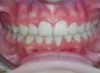

Cas 1

Enfant de 8 ans, béance incisive importante due au pouce et à la langue. Correction progressive après arrêt du pouce et travail sur la position de la langue.